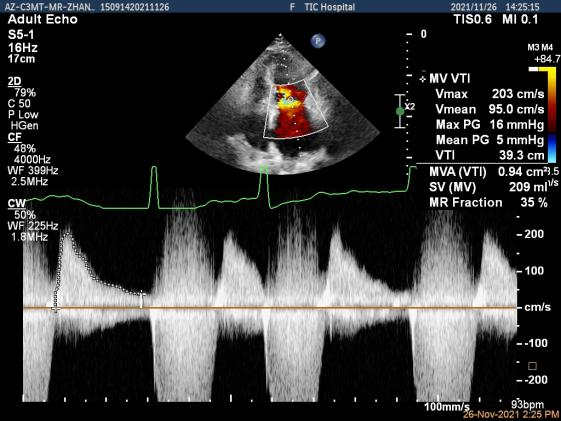

Qlab软件勾画估测瓣口面积约:4.42cm²

二尖瓣口平均跨瓣压差:5mmHg

第一个夹子放置侯二尖瓣口平均跨瓣压差:4mmHg